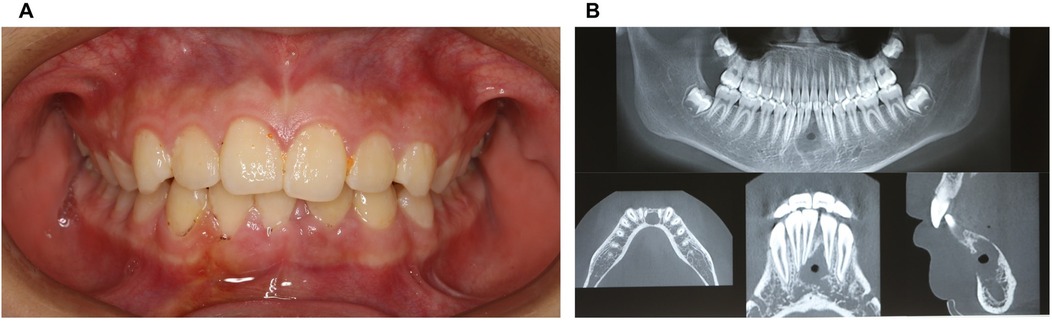

The patient returned for a postoperative review two weeks after surgery, with the surgical site showing good healing and no reported discomfort (Figures 4A,B; Figures 5A–C).

Figure 4. Physical and CBCT examination two weeks after surgery. (A) Photos of intraoral view; (B) CBCT examination.